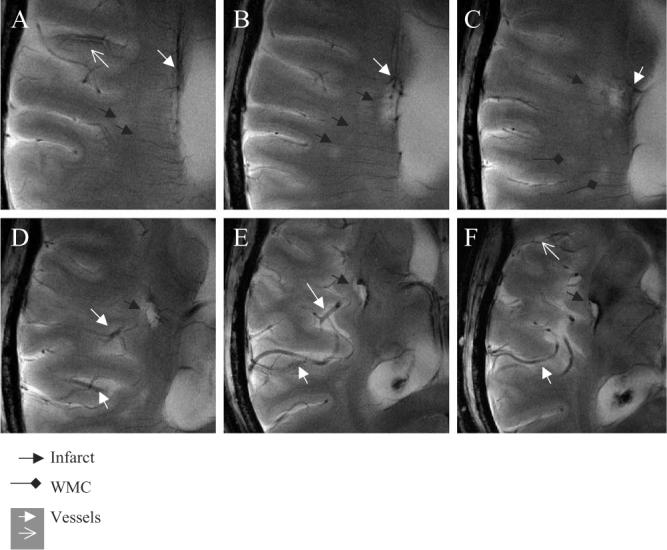

Fig. 6 shows six high-resolution 8-T MR GE images (A–F) demonstrating microvascular patterns associated with the right basal ganglia embolic infarct in a 51-year-old man (Table 1, case 4). Fig. 6A and B illustrates the small vessel terminating within the lacunar infarct. Punctuate foci of low-signal intensity that are seen at the endings of this vessel are suggestive of hemosiderin residuals following an embolic event. Another vessel with a higher signal intensity that is surrounded by a low-signal intensity area is seen laterally to the infarction (A). Fig. 6D–F demonstrates communicating branches of the right middle cerebral artery. Additional minute white matter hyperintensities within the right temporal region are suggestive of the small-vessel disease. The 1.5-T comparisons of this case and the case 11 have been reported [16,17].

Fig. 6.

The 8-T GE slices (A–F) demonstrate vascular supply to the lacunar infarctions and vascular patterns in the infarcted region. A small vessel is seen terminating within the lacunar infarction (black arrow) (A), ending with the low-signal intensity foci (A, B). A cortical penetrating vessel with the lumen of high-signal intensity and the low-signal intensity edge (white empty arrow) is seen in this region (A, F). Punctuate areas of signal hyperintensity, suggesting white matter changes (black diamonds) and small infarctions, are seen in this area (black arrows) (A–C). Branches of the right middle cerebral artery supplying the infarcted area appeared prominent (D–F). A larger area of low signal suggestive of iron deposits extends beyond infraction into the basal ganglia. The 8-T GE: BW=50 kHz, FOV=20×20 cm2, slice thickness=3.0 mm, TR=800 ms, TE=20 ms, matrix=1024×1024 (in-plane pixel size, 195 μm).

4.3. Infarct site

The high-resolution 8-T RARE image at the level of the ventricles shows details of the left basal ganglia infarction. The 8-T images were acquired 6 months after an acute stroke, from a 45-year-old man with a history of the right-sided hemiplegia (Fig. 7) (Table 1, case 5). Initial 1.5-T scans were not repeated. The left basal ganglia infarct was seen as a high-intensity signal area, adjacent to the ventricle. A low-signal intensity area, surrounding the infarct, extended into the white matter. Two low-signal intensity areas within the infarct, adjacent to the ventricle, were suggestive of hemosiderin deposits. Punctuate areas of high-signal intensity were suggestive of infarct consolidation and vacuolization. Small vessels that were visible within the infarcted area had a characteristic low-signal intensity appearance and similar size as cortical vessels within noninfarcted regions.